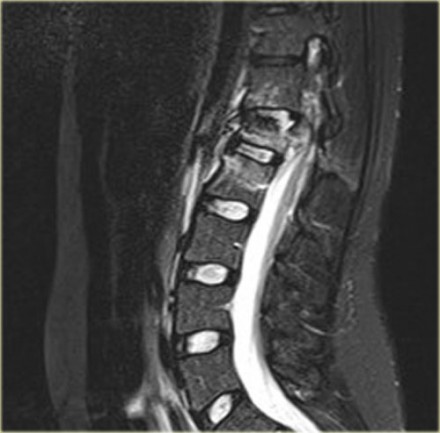

The findings are:

- Morphology: Burst - 2 points

There is retropulsion of a body fragment (black arrow) - PLC: widening of both facet joints (yellow arrow) and a fracture of spinous process (blue arrow) - 3 points

- TLICS based on imaging: 5 points

Discussion: based on only

these two images it is hard to say whether this is burst with

PLC-injury or maybe distraction on the posterior side.

In either case the TLICS-score is high and this patient is a surgical candidate.